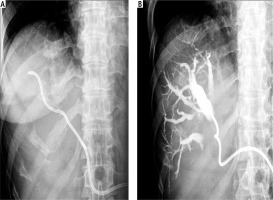

Fig. 1

Percutaneous transhepatic biliary drainage performed using an 8F catheter. A) 8F catheter introduced into the bile duct. B) Checking for catheter patency by injecting contrast through the catheter into bile ducts during follow-up cholangiography

PTBD was performed under ultrasound guidance with careful localization of the biliary tree and proper selection of the entry site. The procedure was performed using local anaesthesia. No conscious sedation was applied. The route for BD depended on the location and available ‘window’ for optimal access to the biliary tree. The access site (right or left lobe puncture) was chosen according to the pre-procedural imaging. Generally, the most commonly used method was the trocar technique using an 8F multisidehole catheter (Boston Scientific, Boston, USA), guiding it into the bile duct (Fig. 1). If the introduction of an 8F catheter into the bile duct was difficult or impossible due to the position or the diameter of the bile duct, a modified trocar method using a multisidehole 5F catheter (Boston Scientific, Boston, USA) was used instead. With this technique, a 14 gauge needle was first introduced into the bile duct. Subsequently, a 5 F catheter was introduced through the needle into the bile duct. After introducing the catheter and the establishment of BD through the catheter, the needle was removed (Fig. 2). The catheter was then secured to the skin and connected to a bag attached to the skin for continuous PTBD. In cases which required introduction of more than one catheter in order to improve BD, additional catheters were introduced by the same method in other selected bile ducts. If a catheter problem occurred, it was resolved by repositioning and flushing of the catheter or by introducing a new one.

The number and size of the catheters were determined individually for each patient by the clinicians and interventional ultrasonographists. Their decisions were based upon clinical considerations, the size and location of the bile duct and its relationship to the surrounding vascular structures. Colour Doppler sonography was performed prior to intervention in order to determine the catheter pathway through the liver tissue towards the targeted bile duct, avoiding vascular structure damage. In general, colour Doppler sonography was not used during the intervention as it was more difficult to follow the catheter tip passing through the liver tissue. Adequate drainage is usually confirmed by a steady decline in serum bilirubin concentrations. Catheter patency was checked by injecting contrast and observing its passage through the catheter (Figs. 1, 2).